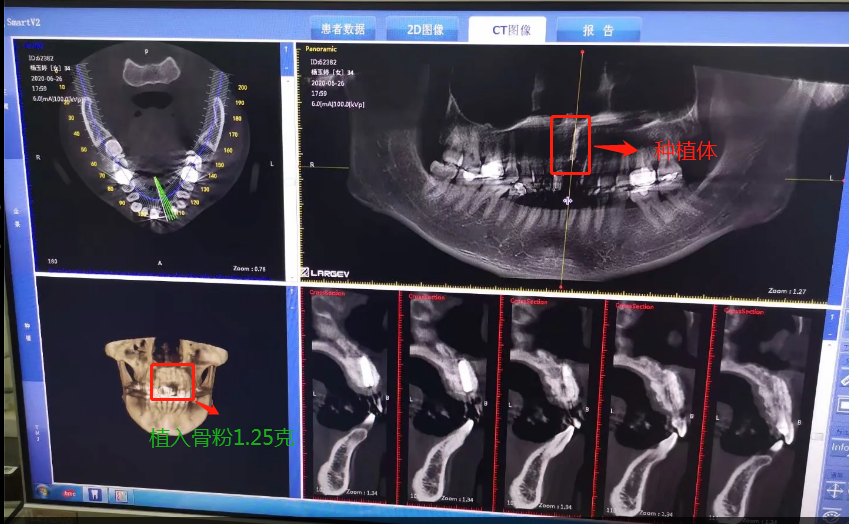

植入種植體后拍的CT

2020年6月26日,終于等到了,我要種植了牙根啦,我牙根弄了法國安卓建品牌的種植體,之前還去幾家口腔門診和烈士陵園的光華口腔也咨詢過和對比價(jià)格,瑞士ITI品牌太貴了(還有別的品牌M美國皓圣、韓國登騰、德國ICX、瑞典諾貝爾等),本來選美國皓圣,但我的是門牙,要選材質(zhì)比較好,考慮美觀問題,后選擇中等價(jià)位的安卓健。手術(shù)很快,而且傷口不是很大,我四天就康復(fù),做完當(dāng)下就可以說話,完全沒有阻礙。因?yàn)檠栏N進(jìn)去必須要等半年時(shí)間跟我骨頭長在一起,因?yàn)槲耶?dāng)時(shí)做手術(shù)的時(shí)候種植入的骨粉還是軟的,還沒有變成硬骨頭?,F(xiàn)在的階段是等待上基臺,上完基臺半個(gè)月時(shí)間上牙冠。2020年12月26日上基臺。預(yù)計(jì)要2021年1月份可以全部完成種牙過程,期待著我?guī)涎例X的那一刻。